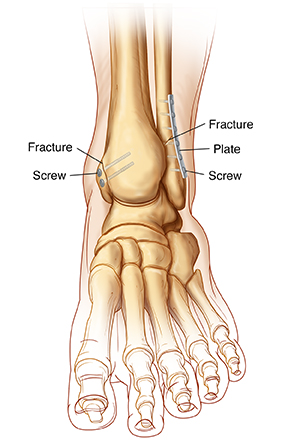

Open reduction and internal fixation (ORIF) is a type of treatment to fix a broken bone. It puts the pieces of a broken bone back together so they can heal. Open reduction means the bones are put back in place during a surgery. Internal fixation means that special hardware is used to hold the bone pieces together. This helps the bone heals correctly. The procedure is done by an orthopedic surgeon. This is a healthcare provider with special training in treating bone, joint, and muscle problems.

| Examples of internal fixation hardware. |

The pieces of the broken bones will be secured to each other (fixation). Your surgeon may use screws, metal plates, wires, or pins.